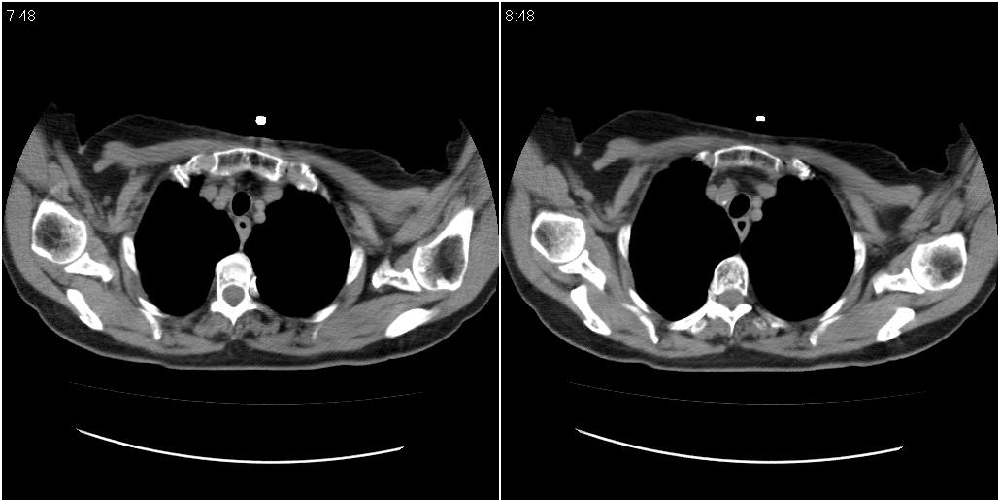

女性,72岁。去年9月份发现肺部病变,诊为肺结核并进行正规治疗至今,但复查后发现ct表现几乎没有变化。

右侧中叶支气管明显狭窄,建议行纤支镜检查!

右中间段支气管局限性狭窄,右中叶支气管亦稍显狭窄,但并未见明显占位表现,半年多了,无变化也许是好事,可能为炎性狭窄,建议继续随访。

右中叶炎性改变,支气管狭窄但较光滑,占位可能性不大。

右肺中叶节段性肺不张,考虑结核或慢性炎症,建议做纤支镜检查。